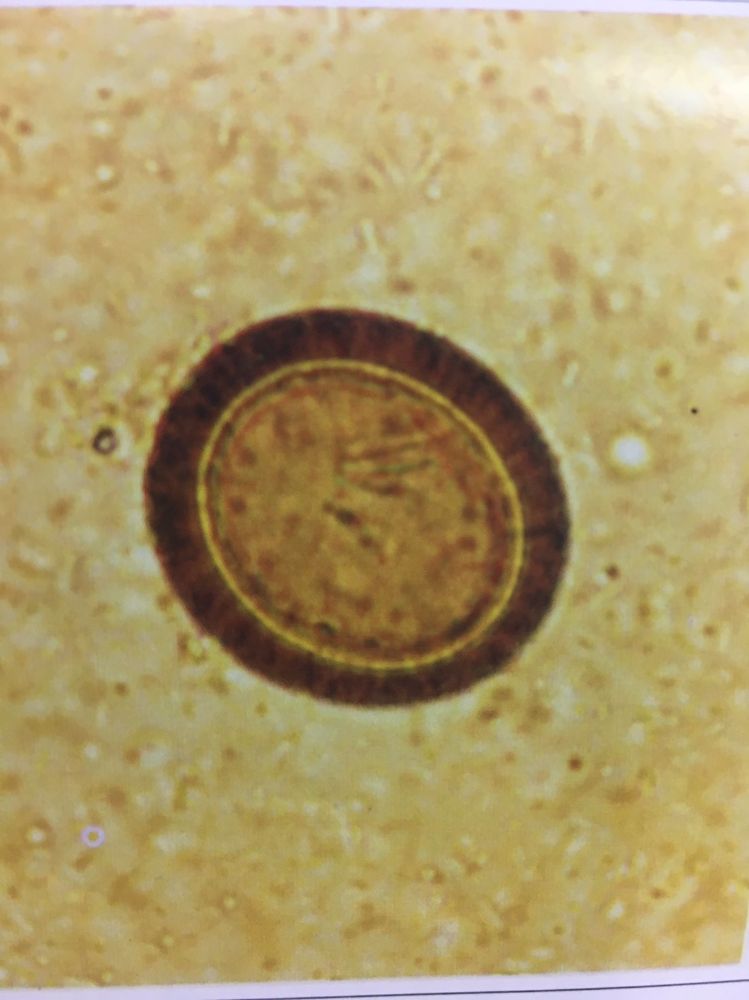

คุณรู้จักพยาธิตัวตืดดีแค่ไหน